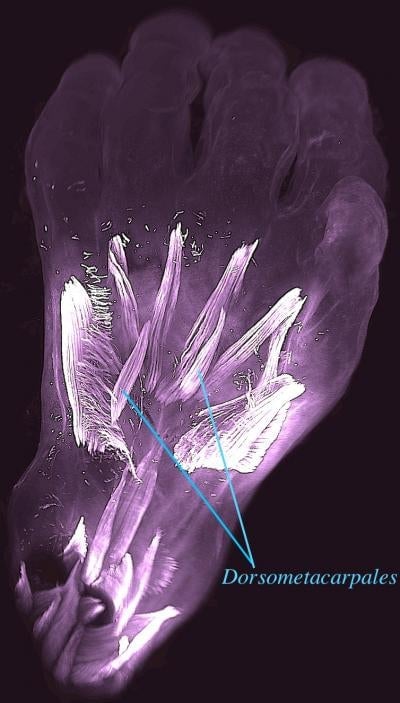

In the hand and foot of a seven-week-old fetus, for instance, they were able to find 30 individual muscles. But by week 13 of gestation, a third of the muscles had vanished or fused together. A pair of these atavistic muscles, as they’re known, is called the dorsometacarpales. And though it’s still found in many limbed animals today, including lizards and salamanders, it seems to have stopped appearing in our adult ancestors 250 million years ago.